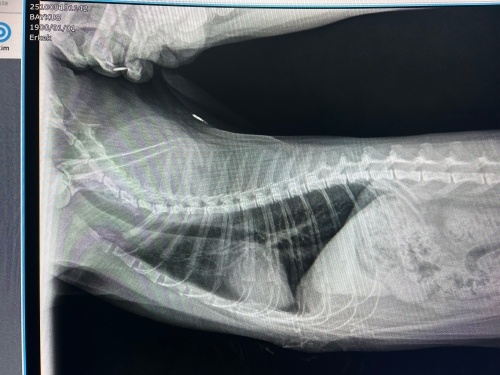

Selam arkadaşlar önce ki sorumda kedimin 2 3 ayda bir koştuktan sonra ağız açık solunum yapıp, serin yerlerde yatıp, öğürüp, o gün bir şey yiyip içneyip diğer gün hiç bişey olmamış gibi normale döndüğünden bahsetmiştim. Vetde kalp enzimine bakıldı yüksek çıkmıştı alanında iyi bir vete gittik eko için kalbinde hiç bir sorun yok çok şükür. Vet birde akciğerlere bakalım dedi röntgen çekildş ve sorun ciğerlerdeymiş. Arkadaşlar ben resmen kendim yapmışım bunu nasıl fark edemedim kendimi çok suçluyorum. Kedim benim odamd yatıyor ve ben onun bebekliğinden berli odamda ki balkonda sigara içiyorum ve balkon dıştan kapatılmıyor yarı açık oluyor 5 yıldır kedim sigara dumanına maruz kaldı. Ben havalandırıyodum ama yinede duman içeri giriyodur ve odamın kapısıd çoğu zaman kapalı oluyordu. Ciğerlerinde tren rayı dediği şeyler belirginleşmiş donut gibi yuvarlar şekiller var vet öksürük var mı dedi yok defim cidden öksürük yok yani 2 3 ay da bir oluyor dedim ayrıca o öğürmesini ciğerlerini açmak içinmiş. Vet bana ilaç vermedi sigara dumanından kokulardan uzak tut dedi şimdi ilaç vermicem dedi ama böyle devam ederse astım olur dedi çok korktum cidden eğer şimdi ilaç verirsem dah kötü olursa kullanıcağımız ilaç kalmaz ilaca bağışıkşık gösterir dedi. Artık odamda ki balkomda sigar içmiyorum yerleri sirkeyle siliyorum ellerimi yıkamadan dokunmuyorum her yeri sabah 23 saat havalandırıyorum. En azından kalp falan çıkmadı çok şükür ama buda beni korkuttu ciğerler kendini yenileme özelleğine sahipmiş ben eğer böyle dikkat edersem düzelirmi ciğerleri? Resim bırakıyorum.